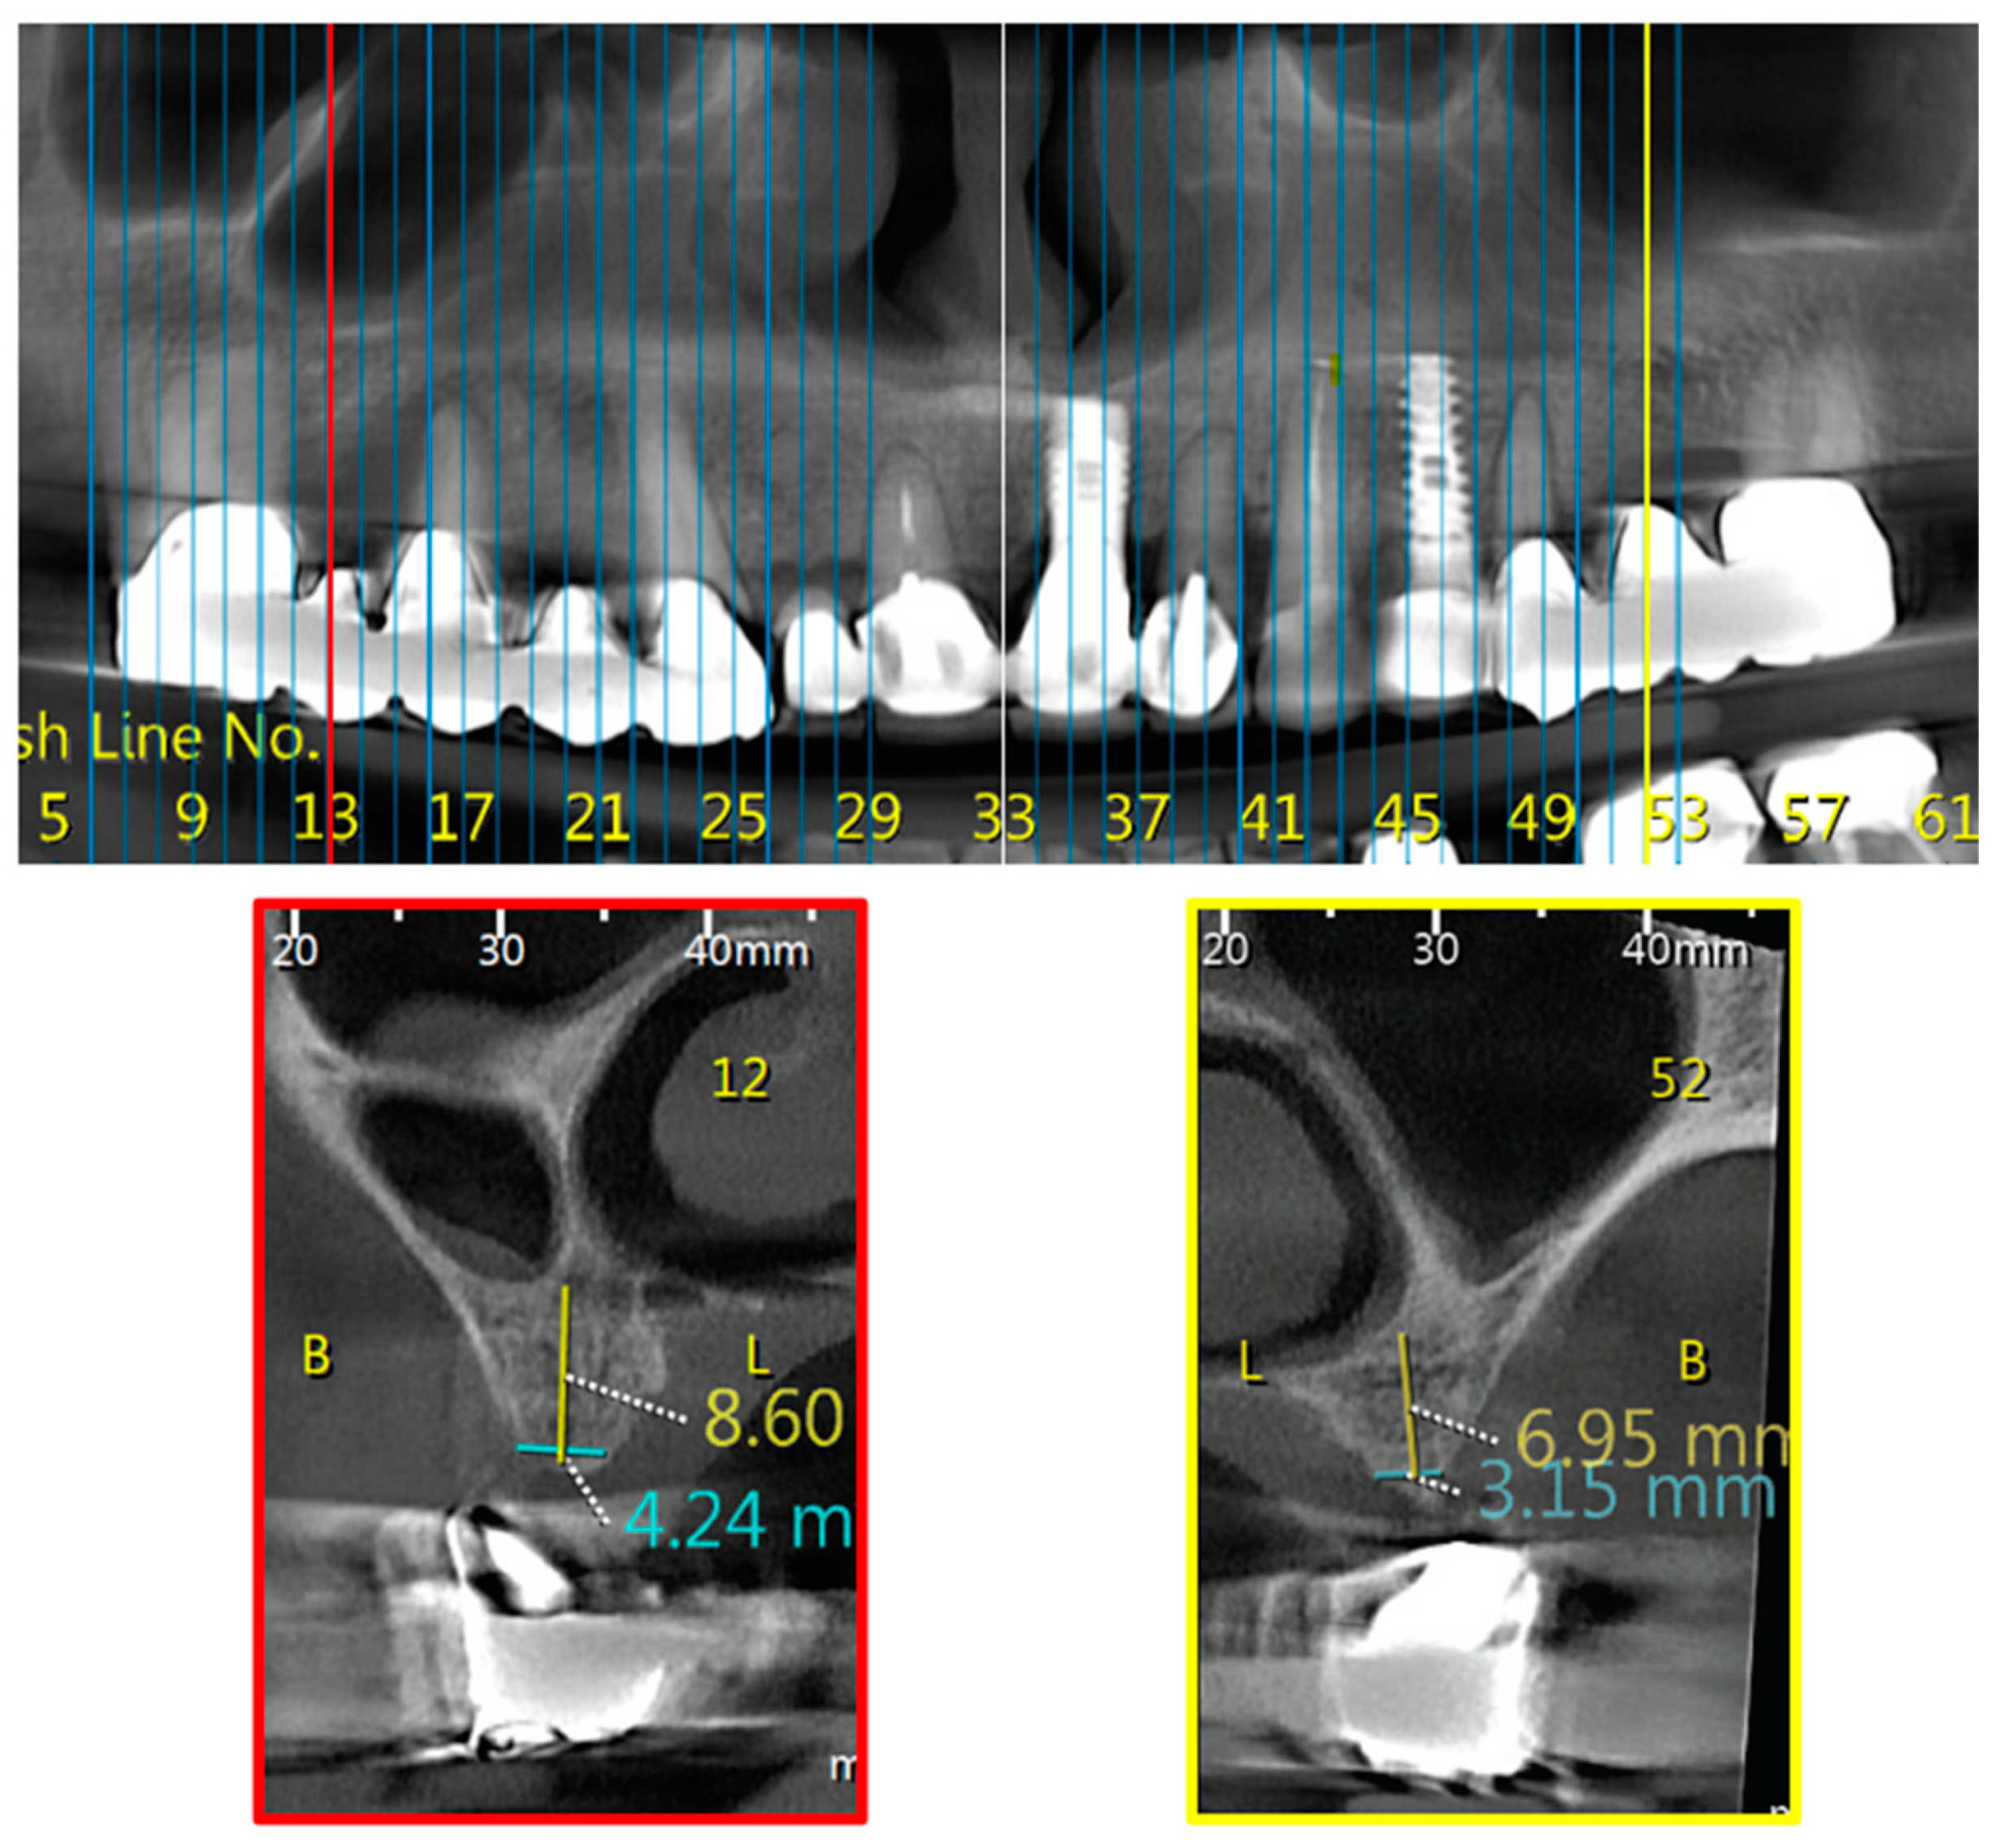

Classes define the MD location of the nasal/sinus border for each hemi maxilla as demonstrate in Figure 1, Figure 2 and Figure 3. The “border cross section” is the most mesial cross section, in reference to maxillary midline, that above the alveolar crest has both nasal cavity and maxillary sinus cavity. The definition of classes is as follows:

Class 3—“border cross section” is located distal to the mesial edge of the 1st molar.

Classes 1 and 2 were defined as normal anatomy and Class 3 as “big-nose variant”.

MD distribution was as follows for all scans examined: Class 1—17.5%, Class 2—64.6%, and Class 3—17.9% (Table 1).

Scientific and clinical knowledge, combined with accurate CBCT analyses, aid dental surgeons in developing patient-specific treatment options [1]. Classes category, in the suggested classification, allow primary definition of the patient sinus/nasal border as normal (Classes 1, 2) or big-nose variant (Class 3), and assist in designing optimal maxillary dental implants treatment plans. Class 2 was found in the majority of cases (64.6%), pointing at the second premolar as the most frequent sinus/nasal border. Class 3 was found in 17.9% of the cases. Such distributions are more frequent than previously reported [6,7], emphasizing the need to be aware of big-nose variant during treatment planning.

Figure 3. Bilateral Class 3; Upper part—CBCT panoramic reconstruction; Lower part—from right to left—CBCT cross sections: cross section number 52—demonstrate left nasal and maxillary sinus “border cross section”, which is located distal to the mesial edge of the 1st molar, defined as Class 3; cross section number 12—demonstrate right nasal and maxillary sinus “border cross section”, which is located distal to the mesial edge of the 1st molar, defined as Class 3. B, buccal; L, lingual.